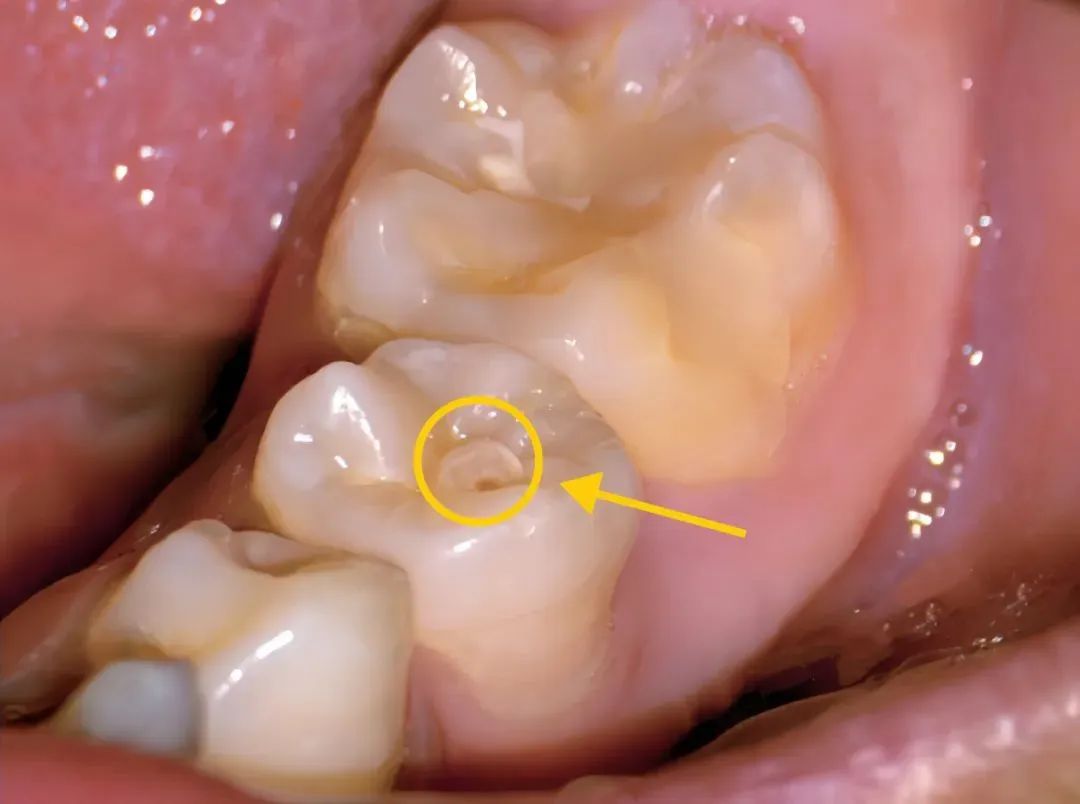

畸形中央尖完好无损时,表现为牙齿颌面中央凸起的小牙尖。当被逐渐被磨损后,表现为圆形或椭圆形黑环,中央有浅黄色或褐色牙本质,可能伴有牙齿敏感的症状。

进一步被折断后,会引起牙髓炎或根尖周炎,表现为牙齿疼痛,不敢咬物。对于年轻恒牙而言,牙髓的感染坏死,将影响牙根的继续发育。

畸形中央尖患牙萌出后,在咀嚼过程中由于受到此尖的干扰,易发生创伤性咬合,导致牙倾斜、扭转,甚至产生错牙合畸形。此外,该尖细而脆弱,咬合过程中易磨损或折断,细菌可直接或间接通过牙本质小管进入牙髓,进而引起牙髓或根尖病变。